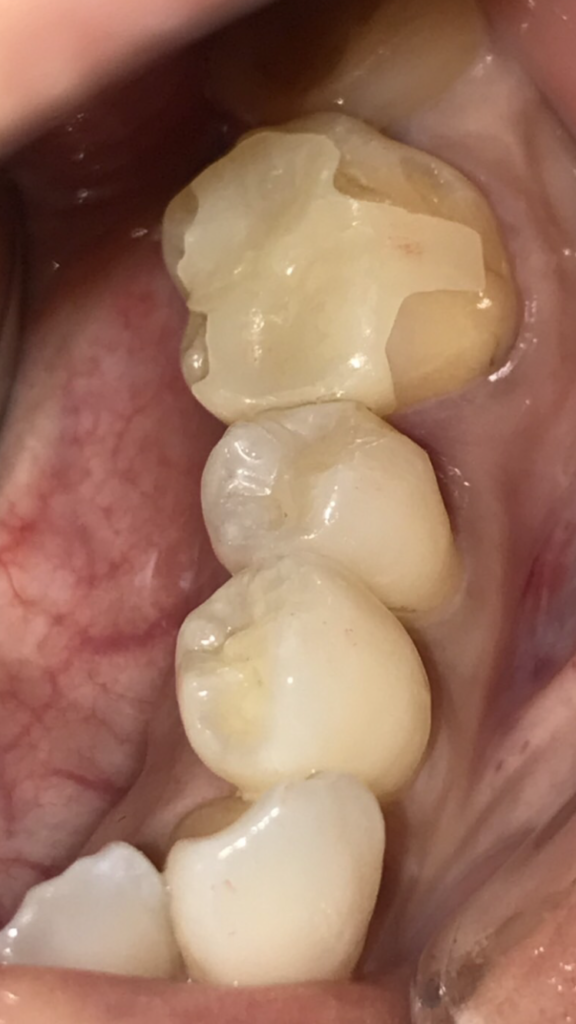

銀歯を外し、虫歯をとった時の写真です。欠損した部分のみをダイレクトボンディングにて修復しました。

ダイレクトボンディングはコンポジットレジンと呼ばれるプラスチックを強化したものを充填するため、強度を考えるとセラミックやゴールドのほうが高いですが、歯を大きく削らずに残存歯質に色調を合わせて修復できる点ではメリットが大きいと思います。

残存歯質がある程度あり、強度が確保できる場合は治療時に提案させていただいております。

料金:¥330000(税込み) 治療回数:1回